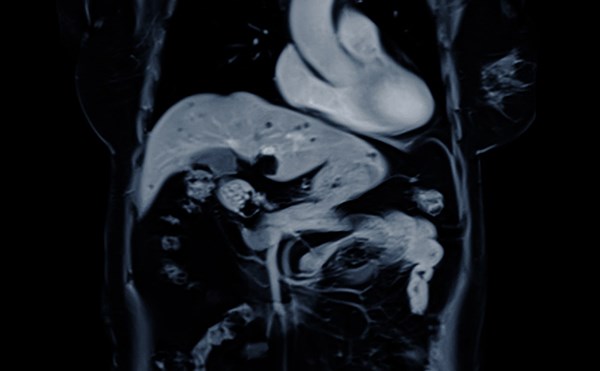

Small Bowel Obstruction

75 year old male with PMH of HTN, HLD presenting with concern of right sided abdominal pain for 3 days, progressively worsening. He appears uncomfortable and is tachycardic on arrival. The goals for t...